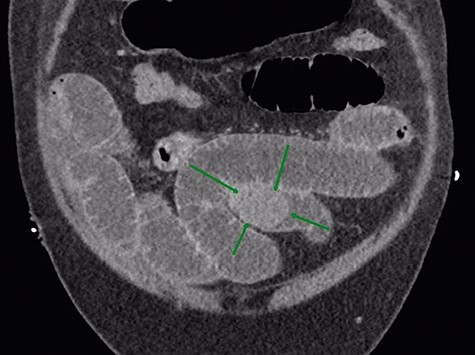

Given that the patient was clinically well, he was managed conservatively overnight with a nasogastric tube and intravenous fluid therapy. The CT scan was closely reviewed by the surgical team the following day and noted the presence of gas within the gallbladder, which was not commented upon by the radiologist (Fig. 2). Furthermore, SBO transition point appeared to be in the distal ileum, where a 3-cm “soft tissue” mass was seen (Fig. 3). His previous CT scan that diagnosed his chronic cholecystitis demonstrated a 3-cm gallstone within the gallbladder, which was not seen on the current CT. The findings of gas within the gallbladder in the setting of SBO and a mass of similar size to the known gallstone raised the suspicion for gallstone ileus. The patient then underwent a laparotomy and enterotomy for a 43-mm gallstone impacted in the distal ileum (Fig. 4). Apart from an episode of ileus, he made a full recovery post-operatively and was discharged home, with an outpatient follow-up in the surgical clinic.

In this scenario, this patient was known to have gallstones and a virgin abdomen, so gallstone ileus was always a possibility. It was the finding of gas in the gallbladder on CT that prompted the surgeons to consider the diagnosis. It is important to note that the diagnosis of gallstone ileus could not be made on plain abdominal radiography, despite the fact that the X-ray was consistent with SBO. This is due to very little air in the biliary tree and only a small bubble in the gallbladder. The gallstone was not calcified and appears of soft tissue density, and was invisible on plain X-ray. Therefore, CT abdomen should be the investigation of choice for suspected gallstone ileus, due to superior sensitivity of CT to detect small amount of gas within the biliary tree and to identify an intra-luminal foreign body of soft tissue density. Neither of these things is possible with plain radiology.